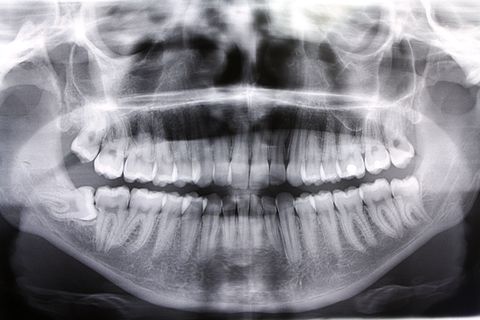

Paciente AB, sexo feminino, 19 anos, com indicação para exodontia dos elementos 18 e 48 incluso e mesio-incliniado.